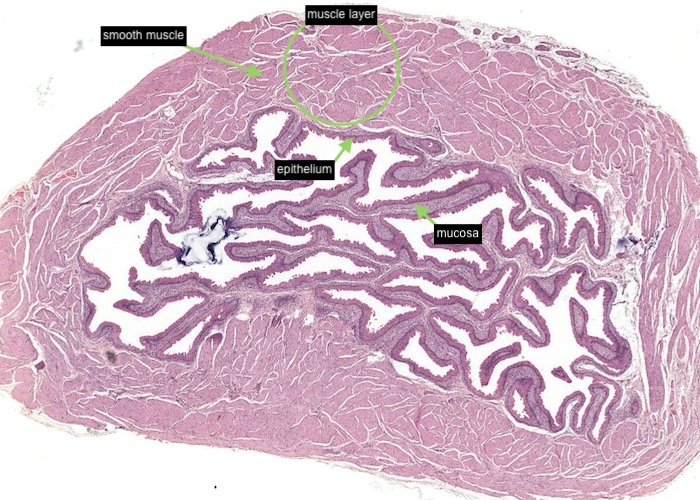

At low magnification, observe the three layers of the ureter: mucosa, muscularis and adventitia. This organization is maintained throughout the urinary passages. The mucosa of the ureter is thrown into characteristic longitudinal folds. It is made of transitional epithelium underlain by a layer of fairly cellular connective tissue (lamina propria). Quite a few lymphocytes are found in this lamina propria. The muscularis layer consists of two somewhat diffuse sheets of smooth muscle: the inner is longitudinal, and the outer is circular. Towards the bladder end it picks up a third oblique layer. This muscle produces peristaltic waves that push the urine to the bladder even when you are lying down. The adventitia is made of connective tissue and contains the nerves and blood vessels that supply the organ. One thing to note is that the ureter runs through loose connective tissue from the kidney to the bladder.

The ureter and also the other passages within the kidney through which urine flows i.e. the calyces and renal pelvis, are lined by transitional epithelium (often referred to as urothelium). The details of the layers of cells within this type of epithelium is best described in the later item "lumenal epithelium" of the bladder but generally it is 2-3 cell layers thick in the minor calyces but much thicker as you see here in the ureter and then the bladder.

Connective tissue and smooth muscle make up the remainder of the wall of the ureter. The smooth muscle is in longitudinal and circular layers so when you examine the section see if you can pick out these longitudinal and circular layers of muscle.